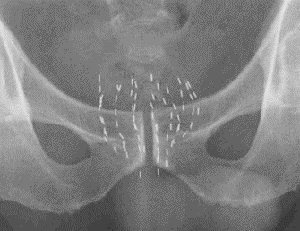

前立腺がんの低線量率組織内照射法は、放射線を放出するヨウ素125線源を前立腺内に挿入し、内部から前立腺全体に放射線をあてる治療法です。線源は直径1mm長さ約5mmで、通常前立腺内に50〜100個程度埋め込みます。低線量率組織内照射法は早期の前立腺がんに対して行われ、治療成績は手術や外照射と同程度と考えられています。ヨウ素125線源からは数mmしか十分な放射線が届かないため、直腸などの周辺臓器の線量を最小限にし、前立腺がんに対して十分な放射線をあてられることがこの治療法の利点です。

治療前検査で得られた超音波画像を元に、必要な線源の個数と配置を決定し線源を注文します。線源注文から納入まで約10日かかります。

線源挿入

治療当日は、全身麻酔を行い治療計画に従って線源を挿入します。線源挿入にかかる時間は約2時間です。麻酔の影響で当日は歩行できませんが、翌日からは今まで通りの生活をしていただけます。刺入部に痛みがある場合もありますが、通常、痛み止めを内服することで対処できます。

線源挿入後1日程度は、挿入した線源が排尿時に尿と一緒に体外に出る可能性があり、線源挿入翌日の夕方まで個室から出ることはできません。

治療に伴い前立腺が腫大したり、挿入後に線源が移動したりするため、治療後にCTを撮影し、前立腺に対しどの程度放射線があたっているかを評価します。